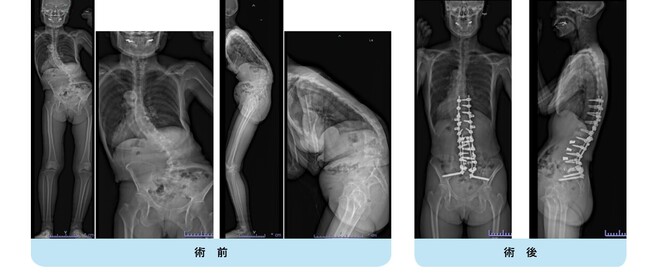

思春期特発性側弯症の全脊椎レントゲンで背骨が大きくSの字に曲がっています。最も曲がっている箇所は80°で、高度側弯に分類されます。後方からの脊柱側弯矯正術で真っ直ぐになっています。

また、側弯の患者さんは一般的にフラットバックと言って背骨の生理的後弯(背中の丸み)が失われています。この症例も胸椎後弯角は5°で典型的なフラットバックを呈しています(正常は20°~30°程度です)。この影響は頸椎の形態にも影響を及ぼし、この症例も頸椎が既に後弯(正常は前弯)しています。(黄色矢印)

ストレートネックという頸椎の前弯が消失して頸部の愁訴が出現する病態は広く知られていますが、更に変形が進行した頸椎と考えて下さい。

以前はこのフラットバック(生理的胸椎後弯の消失)を治すことは困難でしたが、当院では手術方法の様々な工夫により生理的胸椎後弯の復元を行っております。この症例は術後に胸椎後弯角が26°と改善しており、生理的な胸椎後弯が形成されています。さらに頸椎後弯にも良い影響を及ぼし、術後は頸椎前弯化が得られつつあるのが分かります。(黄色矢印)

他、側弯変形は必ず大なり小なりの回旋変形を伴います。脊柱の回旋変形は胸郭(肋骨)の回旋につながり、これにより側弯の患者さんは背中の片方が出っ張っています(多くは右)。リブハンプと言いますが、脊柱変形矯正によりこの回旋変形も改善します。この症例も術前に肋骨がかなり隆起していますが、術後にこの隆起がかなり減じているのが分かります。(赤矢印)

思春期特発性側弯症が高度に進行した症例です。最大側弯角度は113°であり、100°を超える側弯の手術は一般的に神経合併症が危惧されます。神経合併症を極力防ぐため、また侵襲を低減する目的で、同じ入院期間に2回に分けて段階的に矯正手術を行いました。1回目に最も側弯の強い箇所に対して側方から椎体間解離を行い、2回目に後方から全体のバランスが良くなるように慎重に矯正固定術を施行しています。

神経合併症はなく、術後の最大側弯角度は15°に改善(矯正率:87%)、背中の大きなコブも無くなっているのが分かります(赤矢印)。神経合併症が発生しないように慎重に手術を行うのは当然ですが、側弯を治すだけでなく横から見た姿勢を治すことにも留意しています。